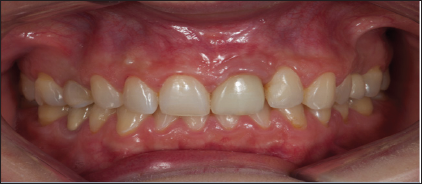

When implant shoulder was reach a screwed-retained temporary provisional was made with a titanium abutment and composite crown, temporary restoration was modified until the desired emergence profile was achieved. For the definitive restoration, a digital intraoral impression scanner LAVA C.O.S (3M ESPE, Spain) with scanning-abutment Core Scanbody (Avinent®- CORE 3D, Spain) was performed. This system required that the impression surfaces must be isolated from fluids and dusted with a light coating of titanium dioxide powder. Powder point's help to interrelating the video images captured by the sensors, with these images a high-quality 3D surface at real time are generated. While the images are captured, a digital model is obtained in the virtual screen of the scanner. The scan of the 2.1 area was performed, followed by the scan of neighboring teeth or working arch, opposite arch and finally the scan of the bite was carried out (Figure 5). Once the images of the digital impression were inspected and approved, were transmitted electronically to the online laboratory in "STL" format. The design of a zirconia abutment with a titanium interface was performed by the software of CAD design of 3Shape (3Shape®, Denmark), files were sent to the milling center (Avinent®, Spain), for the milling of the structure on the one hand, and on the other, the prototype model or milled model was printed with an 3D Eden 260V (Sistemas Objet, Israel) printer, utilizing a composite injection technique. The restoration material for the crown was IPS E-Max Ceram® (Ivoclar Vivadent AG, Liechtensstein) (Figures 6-9).

Figure 9: Frontal View at 1-Year Follow-Up.